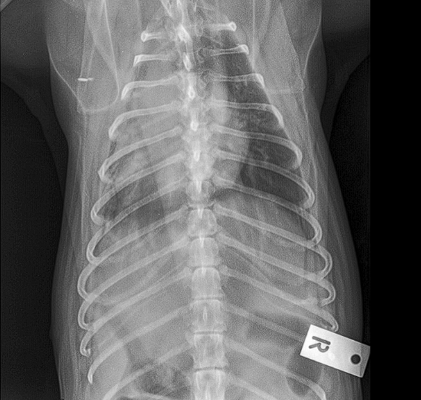

Little area of consolidation but nothing else significant

DX - chronic cough suspicions for airaway disease due to chronic unproductive cough

On left hand side (actually right ariway) airway is compressed

Wouldn’t be ablse to see mass on radiograph as heart borders block ti